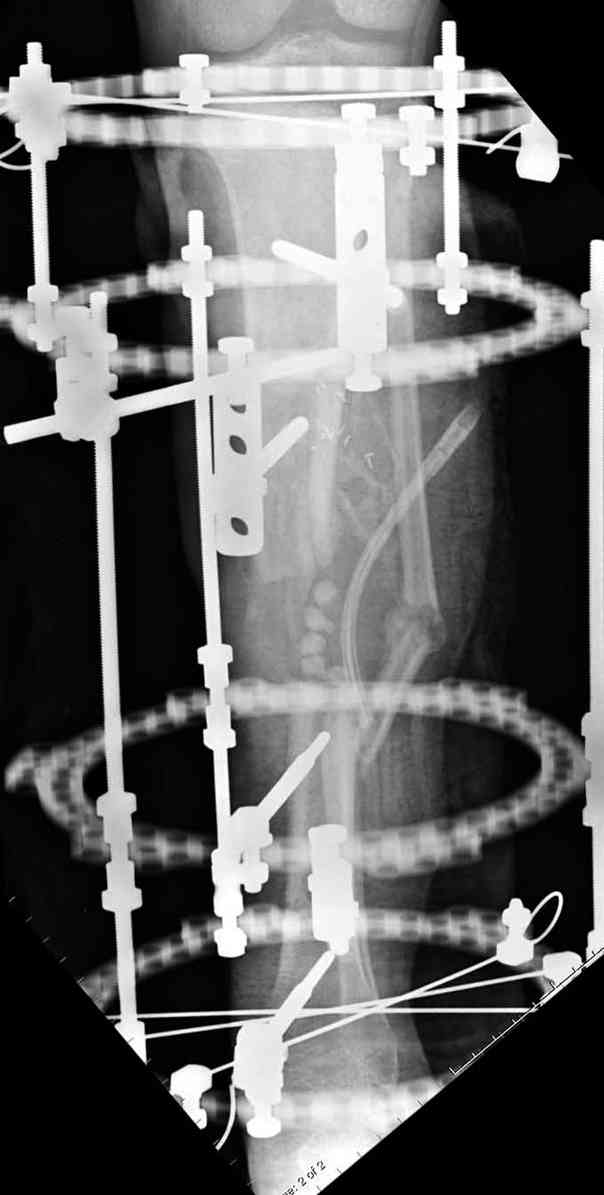

Из аппаратов предпочтительно циркулярный, на дистальном фрагменте можно увеличить количество спиц.

Здесь случай, хотя не тот уровень, но принцип "удлинения после заполнения дефекта Antibiotic Beads" сохранен, можно немного увеличить количество бус.